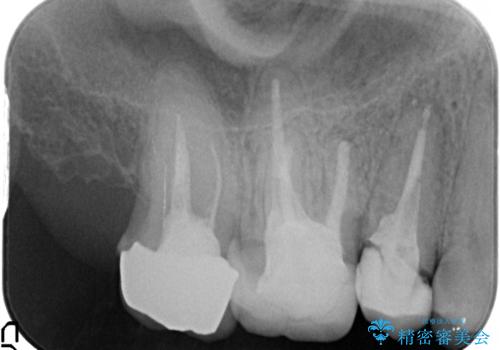

- 以前、他院で保険治療の被せ物を入れた歯が欠けてしまったことを主訴に来院されました。

その他の歯も適合が悪く治療が必要でしたので、3歯まとめて治療を行いました。

歯肉縁下マージンに対して矯正的挺出などの治療の選択肢や、根管治療の提案をしましたが、患者様との話し合いにより歯冠修復のみ行なっております。